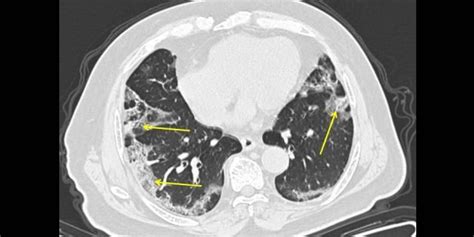

Coronavirus: What X-rays and CT scans reveal about how ...

15 + Lung Images After Covid High Quality ImagesBoth lungs appearing white and opaque (versus black) on chest X-rays (called bilateral lung opacities on chest imaging). Here's what coronavirus can do to your lungs in mild-to-moderate, severe, and critical cases. Keith Mortman, the chief of thoracic surgery The hospital typically uses the CT imaging technology that produced the video for cancer screenings and to plan surgeries.